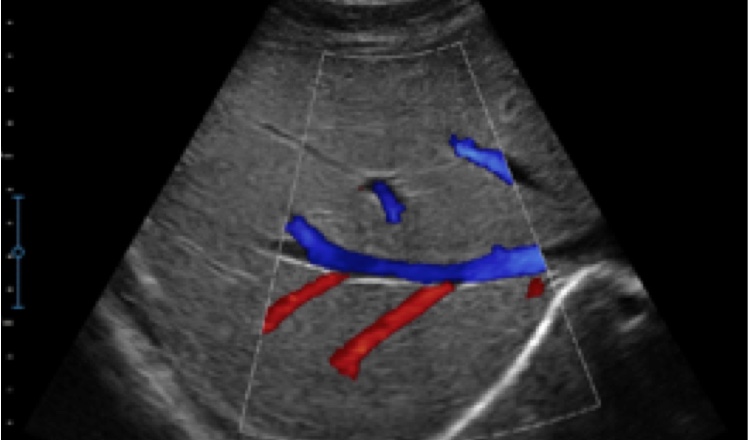

X5采用前端的超声专用芯片,将台式机大规模集成电路完美压缩在笔记本超声的精巧下,提高了系统的运算速度,加载μ-Scan微米成像、脉冲反相谐波等技术,带来优异的临床表现,清晰呈现高分辨率二维图像和层次丰富的血流图像

X5具备实时宽景成像、穿刺增强、彩色M型、组织多普勒等多种高级成像功能,全方位满足多个科室的诊断需求,整机系统向智能化跨越